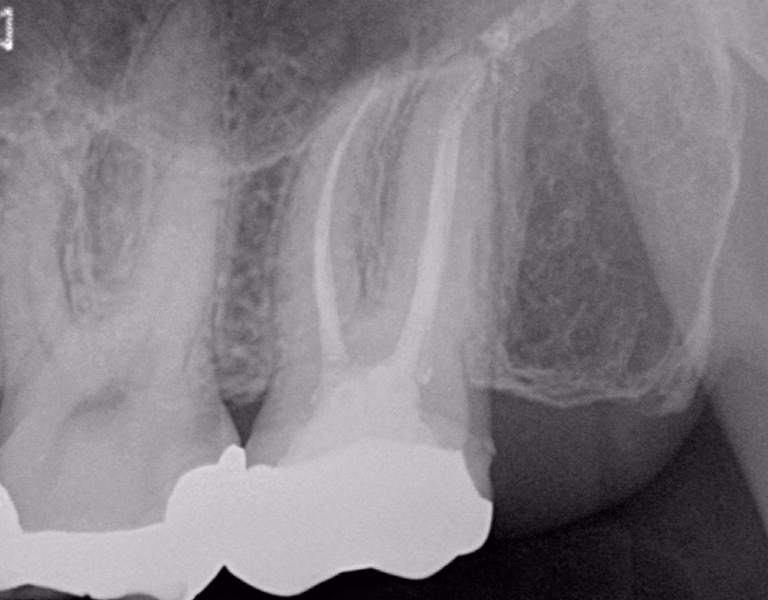

通常の根管治療では消失しなかった大きな根尖病変に対し外科的処置を追加。

1年後には病変の消失と症状の改善が確認できました。

今後も定期チェックで長期安定を図ります。